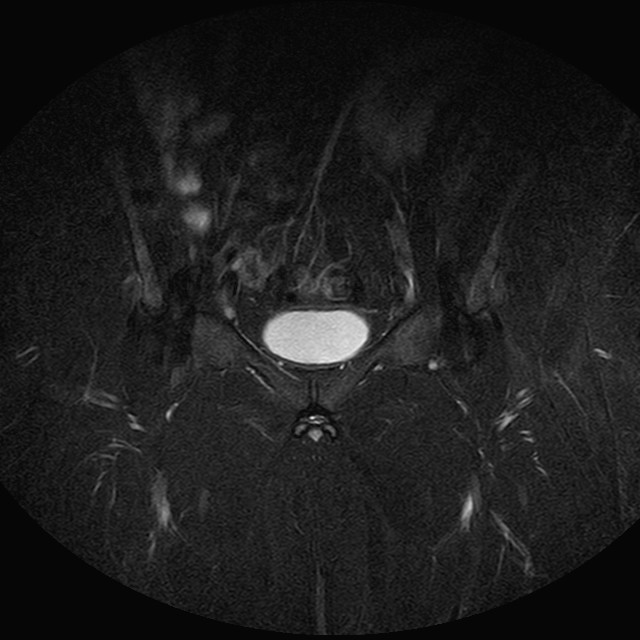

Esami: RMN BACINO

eSTIR

Evidenti e simmetriche alterazioni osteofitosiche in regione coxo femorale con riduzione delle rime articolari. Degenerazione completa del cercine glenoideo. Non attuali segni di versamento articolare. Non segni di edema osseo che escludono attuale algodistrofia od osteonecrosi. Lieve e simmetrica riduzione del trofismo della muscolatura glutea.